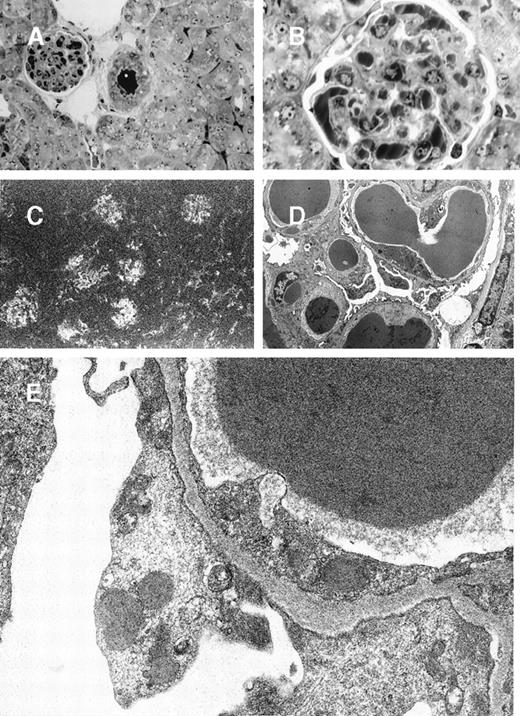

In mice grafted with the 8A4-NP1 hybridoma cells producing noncrystallizing IgG3, tumor cells did not contain any intracytoplasmic crystalline inclusion (data not shown); neither could crystalline organized deposits be found in glomeruli. Only abundant amorphous Ig precipitates predominating in glomerular capillary lumens but also in peritubular capillaries and arteriolar lumens were found without hypercellularity or polymorphonuclear leukocyte afflux (Figure5A and 5B). Thrombi (intracapillary precipitates) were amorphous, without any crystalloid, fibrillar, or microtubular organization (Figure 5C, 5D, 5E). Numerous cytoplasmic dense bodies without any ultrastructural organization were found in glomerular endothelial and epithelial cells and in proximal tubular cells (Figure 5E).

8A4-NP1 cryoglobulin, renal lesions observed in mice kidneys.

(A and B) Light microscopy showing intravascular precipitates not solely in glomerular capillary lumens but also in peritubular capillary and arteriolar lumens. Note the absence of inflammatory reaction. Semi-thin sections, toluidine blue staining (A, original magnification ×400; B, ×1000). (C) Immunofluorescence microscopy with antimouse Ig conjugate (original magnification ×200) showed staining of intravascular cryoglobulin aggregates. (D and E) Electron microscopy showed osmiophilic amorphous precipitates in capillary lumens without crystalline substructure and without any deposits in subendothelials spaces. Note also the amorphous dense bodies in epithelial and endothelial cell cytoplasms (D, original magnification ×2500; E, ×12 000).